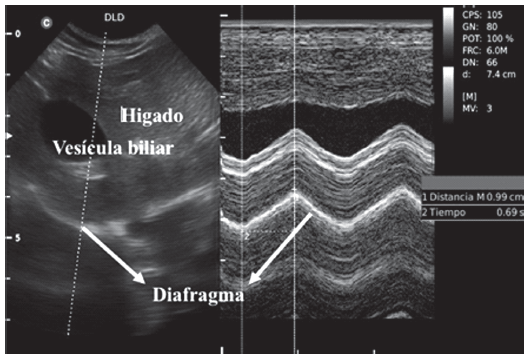

Se tuvieron en cuenta para el siguiente estudio treinta y tres perros adultos, que estuvieran en el servicio de internación, sin patologías cardiorrespiratorias y quince perros programados para cirugía electiva, durante los meses de noviembre a diciembre de 2018 en la clínica veterinaria Kanicat en Bogotá -Colombia. Los perros internados y programados para cirugía fueron seleccionados como aquellos sin antecedentes o signos clínicos de enfermedad cardiorrespiratoria, a los cuales se les realizó ultrasonido pulmonar y cardíaco G-FAST (Focused Assessment with Sonography for Trauma - Global) (Lisciadro, 2016). Los perros con hallazgos ultrasonográficos anormales se excluyeron de los grupos. Con el consentimiento informado del propietario, los perros incluidos en el estudio se examinaron utilizando ultrasonido en modo B y modo M (Fig. 1), con una sonda microconvex 4.5Mhz-8.0Mhz MC6 (Ultrasonido Chison ECO6 VET).

Para la obtención de las imágenes del diafragma se realizaron medidas en tres posiciones, en los perros internados: en estación, decúbito lateral derecho y decúbito dorsal (Fig. 2) y dos posiciones en los perros sometidos a cirugía electiva: decúbito lateral derecho y decúbito dorsal. No se realizó la medida en estación en los perros de cirugía programada ya que al momento de la inducción anestésica no era seguro para el perro ni cómodo para el operador. En las diferentes posiciones se utilizó la vista subxifoidea del cuadrante hepatodiafragmático del protocolo A-FAST (Focused Assessment with Sonography for Trauma - Abdomen), con una inclinación de la sonda de 45° en un corte transversal, presión hacia craneal debajo del proceso xifoideo con la configuración estándar del equipo predeterminada para cada talla de perros (Fig. 3), el parénquima hepático y la vesícula biliar se utilizaron como ventana acústica y referencia para la localización de la cúpula del hemidiafragma derecho. Los perros programados para cirugía electiva se seleccionaron como perros con clasificación ASA I y II (American Society of Anesthesiologists) y riesgo anestésico bajo, la evaluación se realizó en la sala de precirugía y se utilizó el mismo protocolo preanestésico para todos: acepromazina 0.02 mg/kg + tramadol 2mg/kg intravenosos y 10 minutos después la inducción con propofol 4 mg/kg intravenosos, luego de la intubación se realizó de forma inmediata el examen de ultrasonido de diafragma en posición decúbito lateral derecho y decúbito dorsal. (Fig. 4).

El operador registró los movimientos de la cúpula del hemidiafragma derecho, colocando la guía del modo M casi perpendicular al diafragma, se examinaron varios ciclos respiratorios registrando la amplitud de la onda (índice de excursión diafragmática en centímetros), tomado desde su punto máximo de elevación a la línea de base y el período de inicio de la onda hasta la mitad de su longitud de onda (tiempo inspiratorio en segundos) (Fig. 5 - 6), el cociente entre la excursión diafragmática (cm) y el Tiempo inspiratorio (seg) dio la velocidad de contracción diafragmática, variable calculada que también fue registrada.